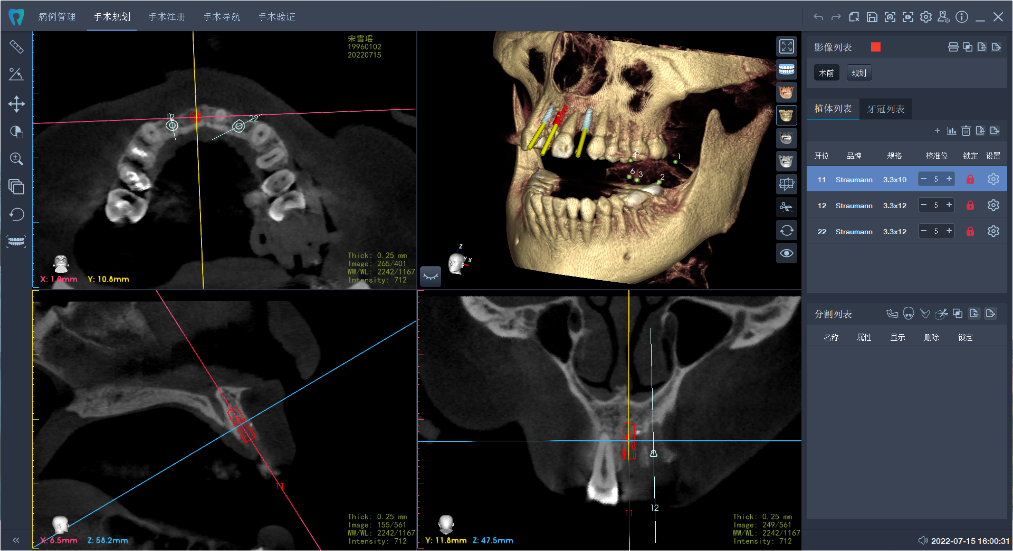

術(shù)前,醫(yī)生將患者的影像學(xué)資料導(dǎo)入機(jī)器人系統(tǒng),進(jìn)行種植體植入全過(guò)程的體外可視化模擬,這樣手術(shù)團(tuán)隊(duì)能充分了解患者牙槽骨的骨量及解剖結(jié)構(gòu)走向,更詳盡地制訂手術(shù)方案。術(shù)中,高益鳴主任、李小曼醫(yī)生共同按既定方案,在機(jī)器人全自動(dòng)模式下,精準(zhǔn)標(biāo)定種植位點(diǎn)并逐級(jí)擴(kuò)孔備洞。而且,機(jī)械臂的減速區(qū)設(shè)定,讓機(jī)器人在入口時(shí)動(dòng)作不會(huì)過(guò)快,“溫柔”且“迅速”地有序按照指令進(jìn)行手術(shù)。手術(shù)過(guò)程相比傳統(tǒng)方式來(lái)說(shuō)縮短了近一半。如今,這位女士恢復(fù)良好。